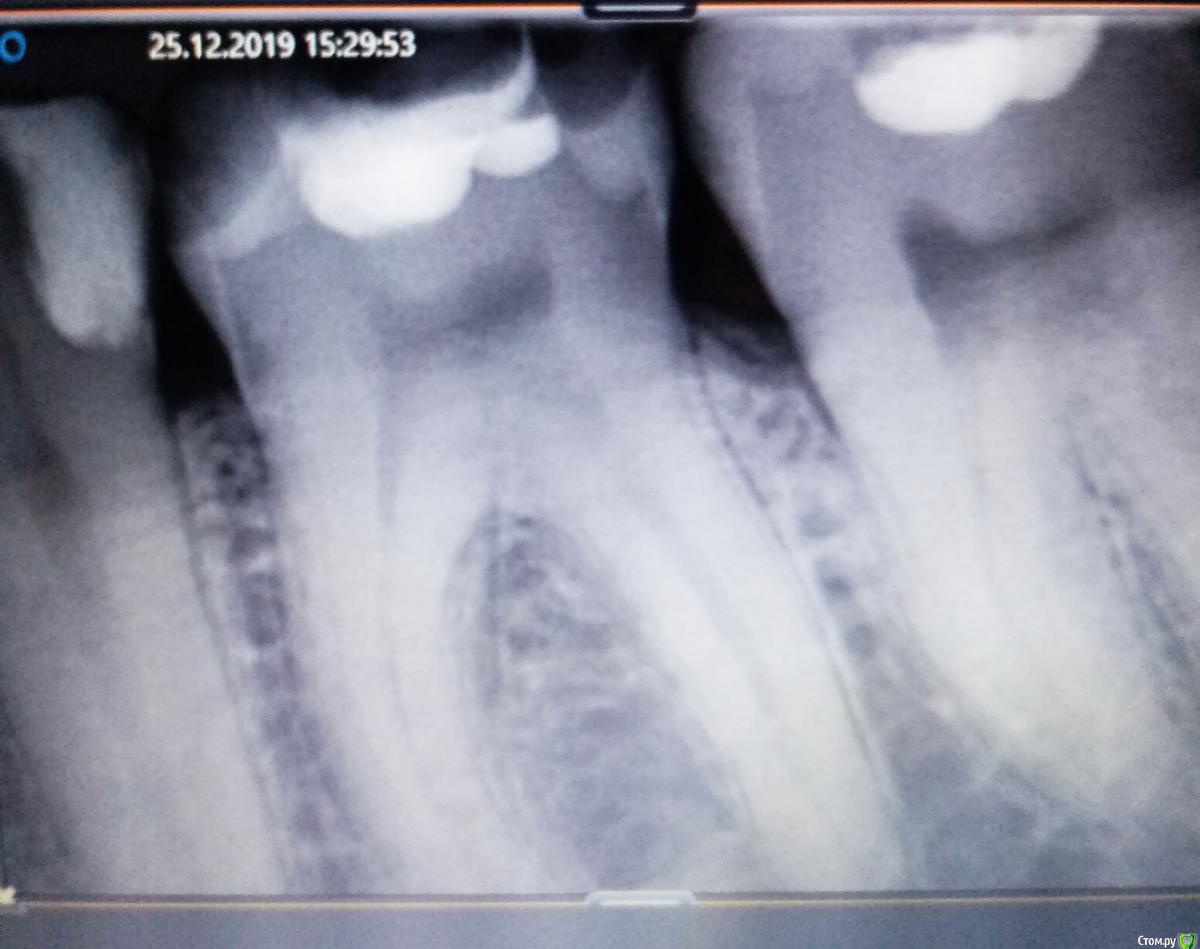

Kattys Опубликовано 6 января, 2020 Поделиться Опубликовано 6 января, 2020 Добрый день!такой вопрос...Болел зуб со старой пломбой после сладкого и соленого 6 ,рядом пятый тоже был с кариесом ,но не болел,сделали сначала пятерку,т.к. там был больше кариес,и 6 стал болеть еще больше,через неделю сделали шестой,но до сих пор периодически побаливает, есть подозрения что оставили старую пломбу,середину , а сделали только бока ,на снимке есть подозрение что остался кариес под пломбой?на снимке немного темное пятно под пломбой , или я ошибаюсь? после пасты от чувствительности зубов стал еще больше сегодня побаливать. Ссылка на комментарий

Kattys Опубликовано 6 января, 2020 Автор Поделиться Опубликовано 6 января, 2020 (изменено) нет конечно ,это после лечения,через месяц.уже прошел месяц с тех пор.,а почему бока не белые как пломба посередине? зуб который на снимке в центре,еще видно пятый частично,но там сбоку видно белая пломба ,все хорошо без потемнения Изменено 6 января, 2020 пользователем Kattys Ссылка на комментарий

red_butler Опубликовано 6 января, 2020 Поделиться Опубликовано 6 января, 2020 С поправкой на качество снимков, я бы рекомендовал для начала вылечить кариес на 7 зубеЧто говорит Ваш врач? Ссылка на комментарий

red_butler Опубликовано 6 января, 2020 Поделиться Опубликовано 6 января, 2020 какой седьмой ? я спрашиваю про шестой,на снимке он по центру,под пломбой вроде есть затемнение? про седьмой мне вообще слова не сказали врачиНа боковой поверхности седьмого зуба кариес. Ссылка на комментарий

red_butler Опубликовано 7 января, 2020 Поделиться Опубликовано 7 января, 2020 про 7 я спрошу еще раз у врача,а под пломбой 6 есть ли проблема? Снимок нужно переделать, зуб сняли не полностью Ссылка на комментарий